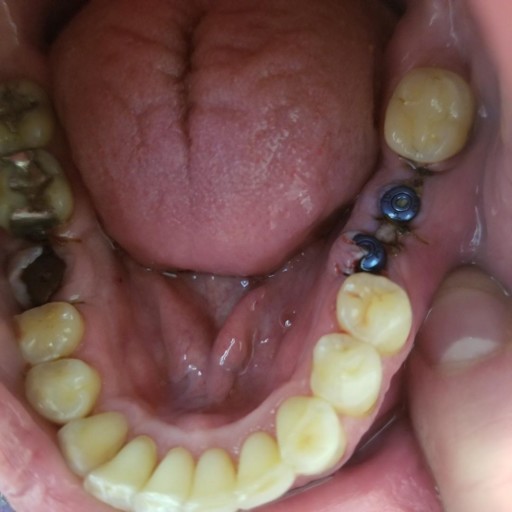

My implants have been placed.

As mentioned in title box, my implants have been placed. I have had a tough time with moving toward the completion due to several issues. My question is, do I have another option that may possibly be less expensive than $15,000 in order to finish this? Please note that I have already spent $10,000 already. I currently have 3 implants on the top and 3 on the bottom. I would appreciate your reply. Thank you.